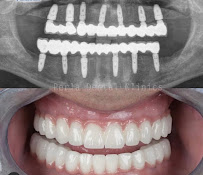

As the name suggests, cosmetic procedures are at the heart of what Tijuana Clinic for Cosmetic Dentistry offers. The clinic specializes in porcelain veneers, dental bonding, teeth whitening, zirconia crowns, and comprehensive smile makeovers that combine multiple treatments for transformative results. The clinic also provides dental implants as the foundation for cosmetic restorations, ensuring that aesthetic work is supported by solid, healthy tooth structure. Gum contouring and other periodontal aesthetic procedures are also available to complete the overall smile design. Each treatment plan is customized to the patient's facial features, skin tone, and personal goals.

The clinic employs digital smile design technology to give patients a preview of their anticipated results before treatment begins. Digital photography and smile analysis tools allow the dentist to plan veneer and crown cases with precision, matching shade, shape, and symmetry to the patient's individual anatomy. The laboratory relationships Tijuana Clinic for Cosmetic Dentistry maintains ensure that porcelain and zirconia restorations are crafted to exacting aesthetic standards. All equipment is maintained to international hygiene standards, and the clinical environment is clean, modern, and designed to reduce patient anxiety.

Cosmetic dental work in the United States โ€” particularly porcelain veneers at $1,000โ€“$2,500 per tooth โ€” is prohibitively expensive for many patients. At Tijuana Clinic for Cosmetic Dentistry in Tijuana, the same quality veneers are available at a fraction of that cost, making complete smile makeovers financially accessible. The clinic's exclusive focus on cosmetic outcomes means patients benefit from a team whose entire practice is built around aesthetic excellence. Combined with Tijuana's proximity to the US border, this makes it one of the most compelling options for patients considering cosmetic dental treatment abroad.